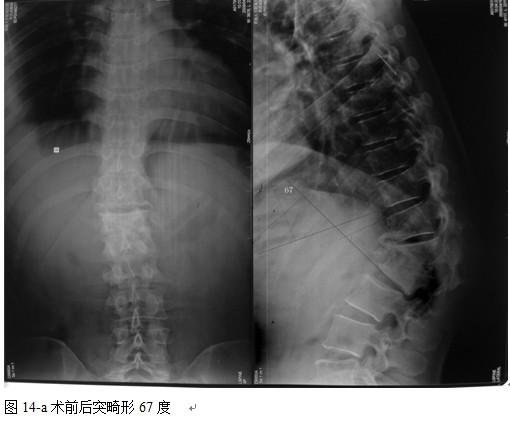

本组46例中男28 例,女18 例。年龄17~67岁,病程6 个月~7年,平均11.3 个月。本组患者均为 L1~S1腰段结核。病灶累及2 个椎体31例(L1-2 6例, L2-3 8例,L3-4 10例,L4-5 5例,L5-S1 2例),3 个或3 个以上椎体15例。合并腰大肌脓肿23列,所有患者均有腰背部疼痛,活动受限,双下肢感觉麻木19例,会阴部感觉减退12例,双下肢肌力减弱12例,腱反射减弱12例,术前后凸角(Cobb 角) <30°者12例, 30°~60°者28 例, >60°者6 例,Cobb角平均32.3°4例患者是二次手术。术前均行X线片、CT或者MRI检查。术后病理检查确诊为脊柱结核。

中国学者金大地[22]等采用一期前路病灶清除植骨前路钢板固定治疗腰椎结核,平均18°的后凸畸形得以矫正,Mukhtar[23] AM等采用前路病灶清除植骨分期或同期后路固定治疗腰椎结核22例,术后后凸畸形矫正度数平均为27°。从我们的随访结果看,术后后凸畸形平均矫正度数为26.9°,后凸畸形平均矫正90%以上, 6个月-49个月后随访,后凸角度平均丢失4.2°。本术式也适用于结核所引起的弹性差的后凸畸形,对于病灶纤维化或骨化的非弹性后凸畸形,后路固定后,先行前路病灶、纤维化或骨化切除、松解,逐步刮除病灶、逐步撑开,达到畸形矫正和植骨的目的。